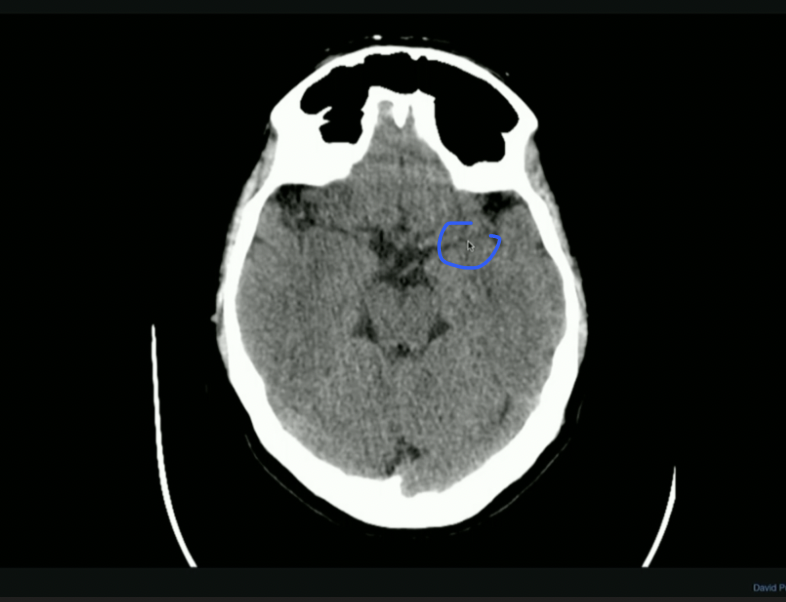

<p>What is the mouse Pointing to? + What does it create?</p>

What is the mouse Pointing to? + What does it create?

• Anterior Horn of Lat. Ventricle

• Houses Choroid Plexus → Creates CSF

• IF: Caudate nucleus swells → Impacts Lat. Ventricle → Huntingtons Disease